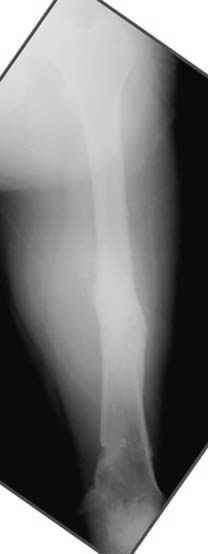

На рисунке N1 предоперационный план лечения ложного сустава шейки бедра- линия ложного сустава, угол и направление введения импланта, клиновидная остеотомия в градусах и миллиметрах, второй снимок после коррекции, расчет, на сколько удлиняется конечность и размеры импланта;

N3 рисунок окончательный снимок, после операции моя рентгенограмма должен выглядеть примерно как эта картина. На N4 снимке клин перед удалением; N5 послеоперации 3 нед.; N6 окончательная рентгенограмма.

(доложен в Ст. Петербурге 2003 и в Москве 2004)

варус при проксимальном отделе 95 градусной пластиной.